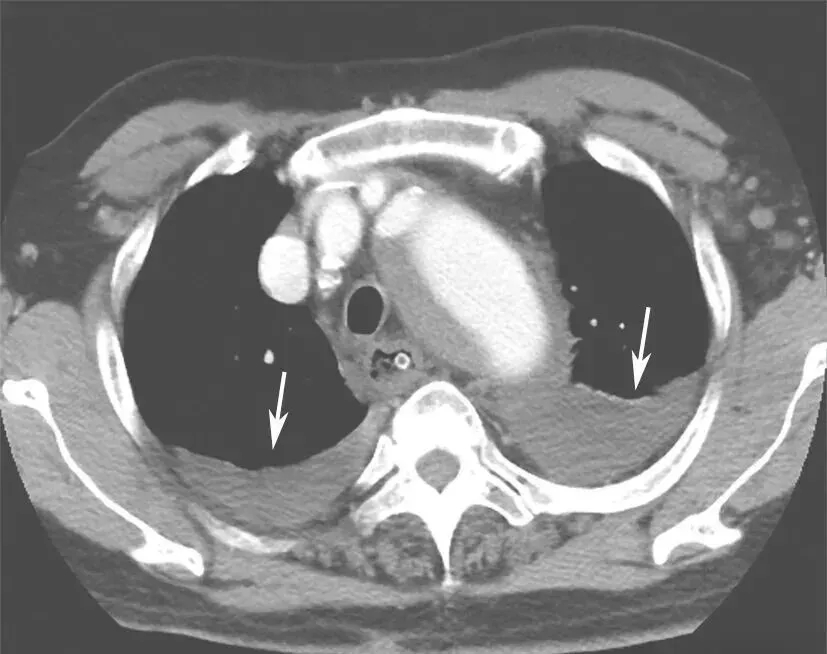

入院后紧急行血管螺旋CT扫描+三维重建,以明确主动脉病变。血管螺旋CT扫描+三维重建如图2所示。降主动脉至腹主动脉夹层动脉瘤并壁间血肿形成(累及主动脉弓至肾动脉开口平面)。升主动脉管径约4.9cm。主动脉弓与降主动脉弥漫管腔增粗,周围可见弥漫壁间血肿形成,向下延伸至肾动脉平面。主动脉弓上三大分支开口与显影良好。主动脉弓外径为5.4cm,内径约3.8cm。降主动脉外径为7.5cm,内径为4.8cm。气管隆嵴下平面降主动脉左前壁局限性钙化上方有一个溃疡,溃疡内有少量对比剂充盈。胸主动脉下段向右侧明显迂曲。腹主动脉与肾动脉平面上方可见内膜片与真假腔形成,假腔内有少量造影剂充填。腹腔干动脉和肠系膜上动脉开口未见受累。右肾动脉开口部分受累,左肾动脉开口未见受累。腹主动脉下段、双侧髂内外动脉血管形态良好。双侧胸腔中等量积(血)液(图3箭头处)。

图3 双侧胸腔积(血)液

诊断明确,经血管外科会诊,考虑手术指征明确,完善术前检查后,在全身麻醉下行胸主动脉瘤腔内修复术(thoracic endovascular aneurysm repair,TEVAR),术中植入2枚GORE-TAG支架型血管,覆盖左锁骨下动脉开口至降主动脉折弯处,造影证实瘤体封闭良好。术中行左侧胸腔穿刺引流术。术后给予镇静、抗感染、营养支持等治疗。收缩压维持在100~140mmHg,术后第2天行右侧胸腔穿刺引流术。双侧胸腔共计引流血性积液1830ml。

临床结局

术后第20天15:20患者出现点头样呼吸,面色苍白,口唇发绀,听诊双肺呼吸音低,以左肺明显。2分钟后心搏骤停,给予持续胸外按压并反复给予药物复苏无效,15:50宣布临床死亡。抢救期间行胸腔超声探查示左侧大量胸腔积液,右侧少量;超声心动图显示,未见心包积液。死亡原因为主动脉夹层动脉瘤破裂。

胸主动脉腔内修复术(thoracic endovascular aortic repair,TEVAR)的主要目的是封闭原发破口,扩张真腔,改善远端脏器、肢体血供,促进假腔血栓化和主动脉重塑。TEVAR适用于锚定区充足(>1.5cm)、非遗传性结缔组织疾病性Stanford B型AD患者。国内荟萃分析结果表明,TEVAR治疗Stanford B型AD的手术成功率为97.66%~99.20%,术后早期患者的死亡比例低(术后30天死亡占2.2%~3.55%),近期疗效良好。IRAD研究表明,与药物治疗相比,TEVAR可提高急性Stanford B型AD患者5年生存率。2014年ESC指南推荐,对于复杂性Stanford B型AD首选腔内治疗;若合并内脏缺血、肢体缺血、疼痛无法控制、主动脉瘤变等严重并发症,需要急诊积极治疗。中国Stanford B型AD患者的平均发病年龄远低于欧美国家,预期寿命长。因此,专家委员会推荐,非复杂性Stanford B型AD患者在最佳药物治疗的基础上首选TEVAR作为进一步治疗措施;另外,TEVAR术中应根据患者病情选择合适类型的覆膜支架,以减小支架远端降主动脉过度扩张或新发破口形成风险。逆行性Stanford A型AD是Stanford B型AD行TEVAR术后最严重的并发症,其发生率为1.4%~10.0%,可能与主动脉壁病变(如合并结缔组织病、急性期主动脉壁水肿等)、术中操作不当、覆膜支架选择不当等因素有关,可发生于术中、术后或随访期,其中约有25%的患者没有症状,仅在复查CTA时发现。该并发症显著增加了患者住院死亡及并发症发生率,一经发现,应按Stanford A型AD治疗原则进行处理。患者在术后20天突发呼吸、心搏骤停,抢救无效死亡,死亡原因考虑为主动脉夹层动脉瘤破裂。该患者临终前病情变化突然,抢救期间行胸腔超声探查示左侧大量胸腔积液,可能为主动脉夹层动脉瘤破裂导致的血性胸腔积液,因患者家属不同意进行尸检,无法获得死亡的直接原因,推测与患者主动脉夹层撕裂范围大、主动脉壁水肿恢复延缓有关。